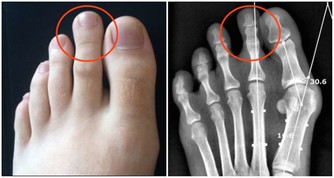

中年人時常覺得腰酸背痛,渾身沒有力氣,而且也懶得動彈,不願意運動,這也說明衰老正慢慢襲來。所以,中年人不要懶惰,而是根據自己的實際情況,進行一些運動,或者做做家務,讓自己活動起來。